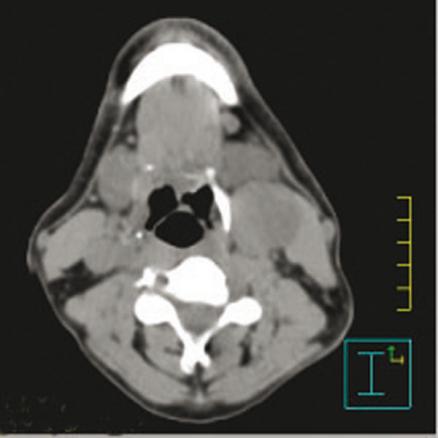

Carcinome épidermoïde du sinus piriforme gauche avec une adénopathie tumorale nécrosée sous-digastrique gauche.